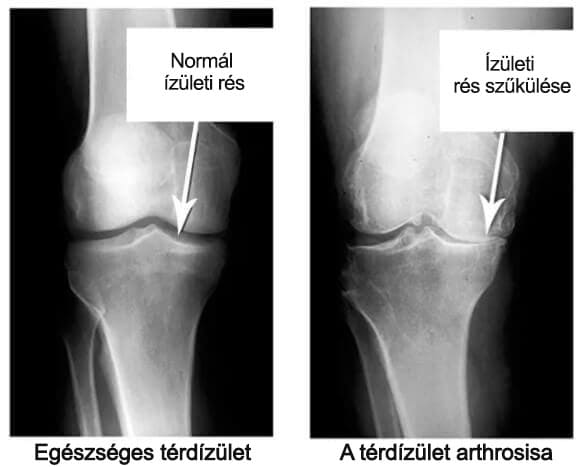

Nézze meg ezeket a képeket, láthatja, hogy a jobb oldali képen nincs ízületi rés, a csontok egymáshoz dörzsölődnek, ami nagy fájdalmat okoz. És ezt a folyamatot nagyon nehéz megállítani!